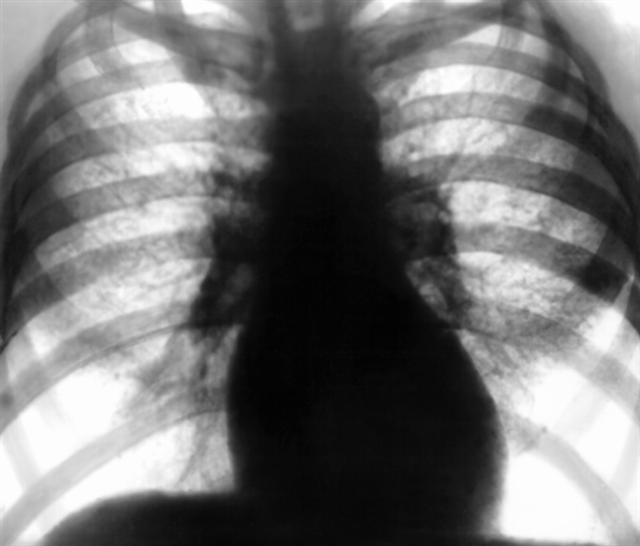

Рис. 1. Обзорная рентгенограмма грудной клетки при II стадии интерстициального пневмокониоза: отмечается сетчатая деформация легочного рисунка, видны многочисленные мелкие затенения, обусловленные перекрестом теней фиброзных тяжей; корни легких неструктурны; базальные отделы легких эмфизематозны. |